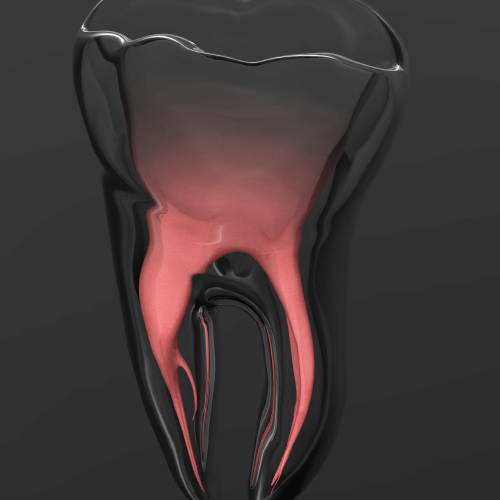

New Directions in Endodontics

Tuesday, April 2, 2024

This Compendium eBook features a continuing education (CE) article on the management of endodontic flare-ups. This eBook also includes an article on intentional replantation as a predictable and cost-effective option for preserving a natural tooth and as a favorable alternative to conventio...